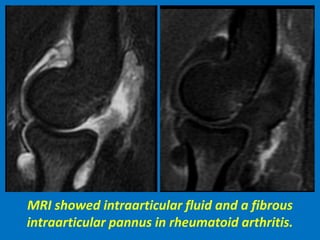

MRI showed intraarticular fluid and a fibrous

intraarticular pannus in rheumatoid arthritis.